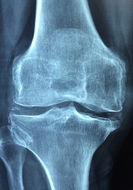

비타민d 많은 음식 이거 보고 적정량 알아봐요 비타민d 많은 음식 및 비타민d 효능 비타민d 부족증상 비타민d 과다 복용 시 부작용 등 비타민d 정보에 대해 정리해드리겠습니다.비타민 D는 태양에서 받은 자외선을 통해 피부에서 합성되거나 일부 식품에서 섭취할 수 있는 필수 비타민 중 하나입니다. 주로 칼슘과 함께 작용하여 뼈 건강을 유지하는 데 중요한 역할을 합니다. 또한 면역 기능을 강화하고, 염증 반응을 저감시키는 등의 효과가 있습니다. 하지만 부족하면 골다공증, 뼈 연화증 등을 유발할 수 있으며, 과다 복용시 중독 증상이 발생할 수 있습니다. 충분한 양의 비타민 D를 섭취하기 위해서는 태양에 노출되는 것과 함께, 식사나 보충제를 통해 섭취하는 것이 좋습니다.

- 뼈 건강 개선: 비타민 D는 칼슘 흡수를 촉진하여 뼈 건강을 유지하고 강화시키는데 도움을 줍니다.

- 뼈 및 근육 통증: 비타민 D 부족은 뼈 및 근육 통증, 근육 경직 등을 유발할 수 있습니다.

- 골다공증: 비타민 D 부족은 골다공증 발생 위험성을 증가시킬 수 있습니다.